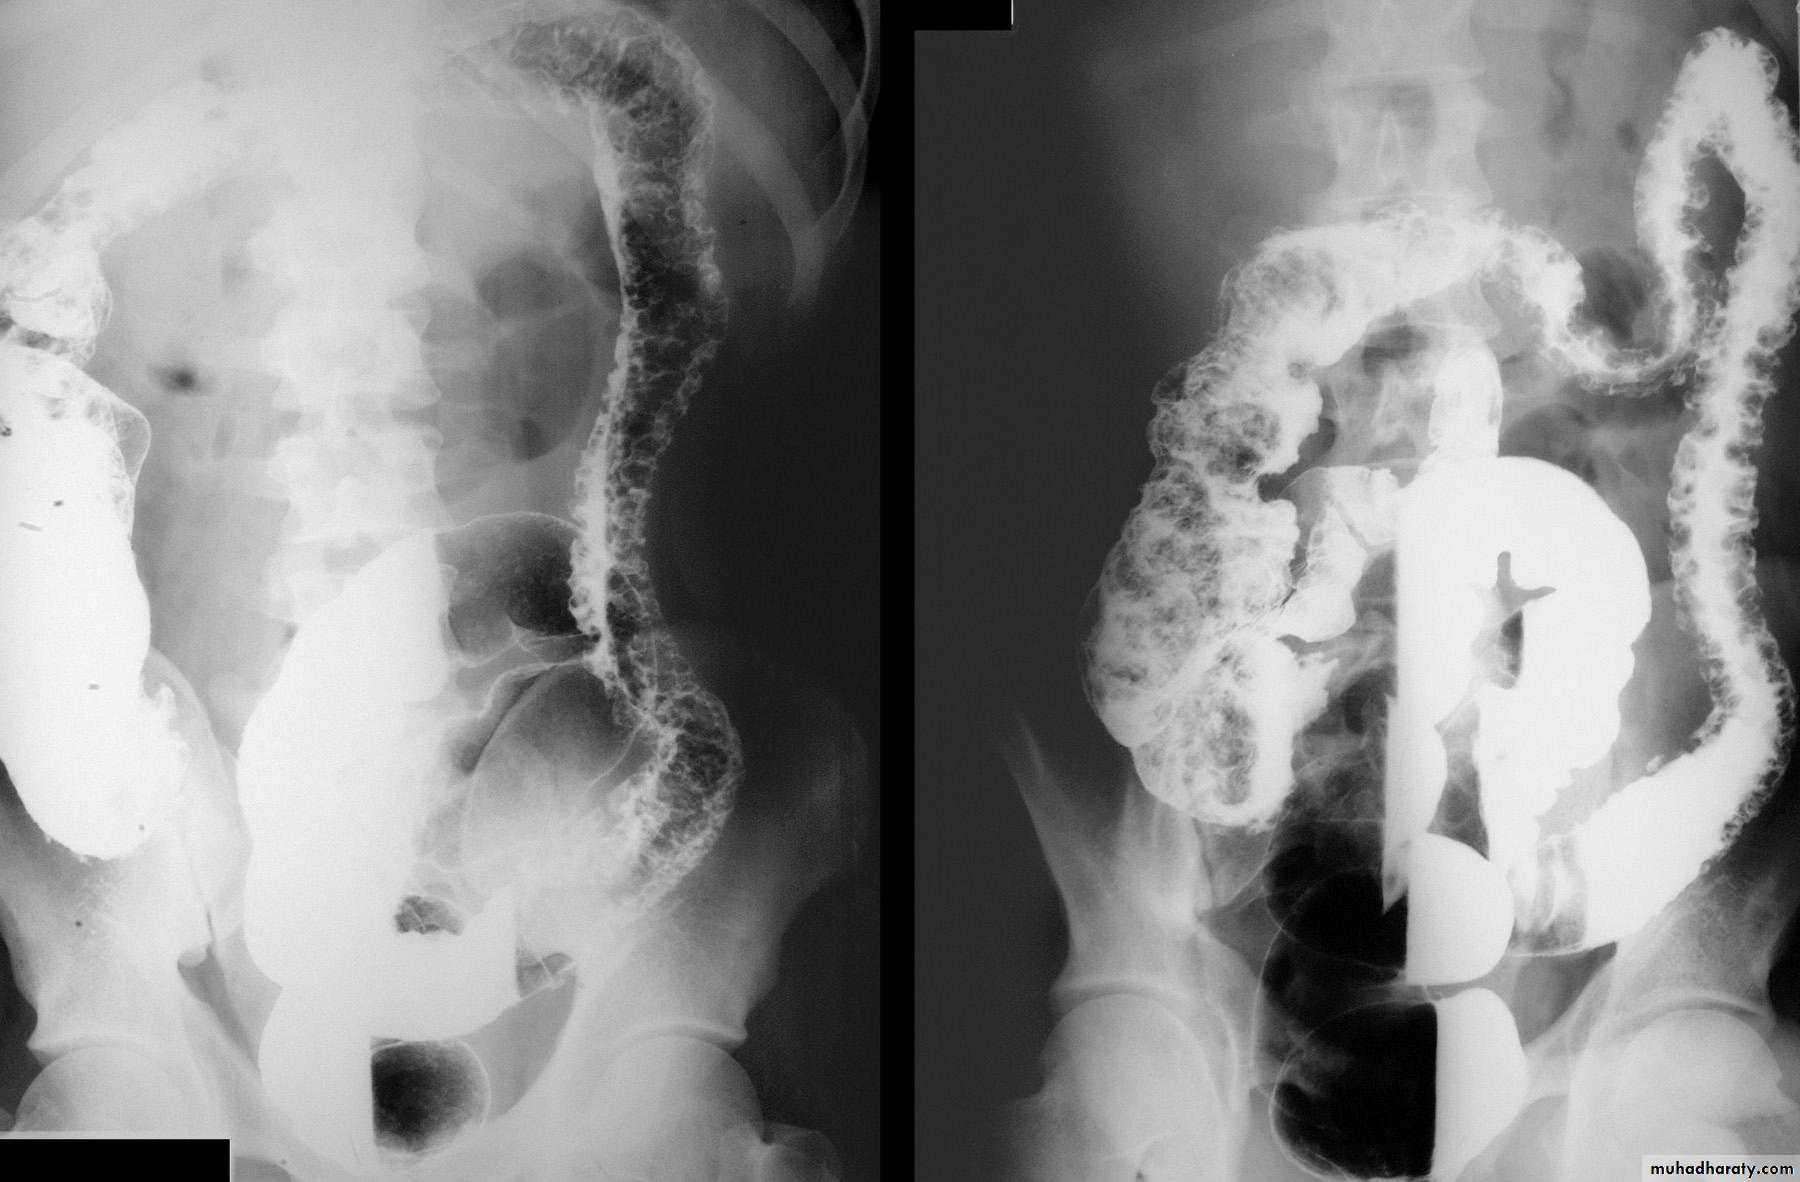

Ulcerative colitis

Always involve the rectum, sometimes extends to involve the whole colonRadiological signs:

1.widespread shallow ulcer is the cardinal sign. Ulcers may be deep in severe cases2. widening of the presacral space due to peri-rectal edema

3. loss of the normal colonic haustra in the affected portions of the colon

4.narrowing and shorting of the colon giving the appearance of rigid tube

5.pseudopolyps ( swollen mucosa between ulcers) seen as filling defects

6.strictures are rare and likely to be due to carcinoma in longstanding disease

7.abnormal dilated ileum due to reflux through an incompetent ileocecal valve

8.toxic megacolon is a serious complication diagnosed by plain abdominal film or native CT. Due to the risk of perforation, barium enema, colonoscopy and CT pneumocolon should be avoided